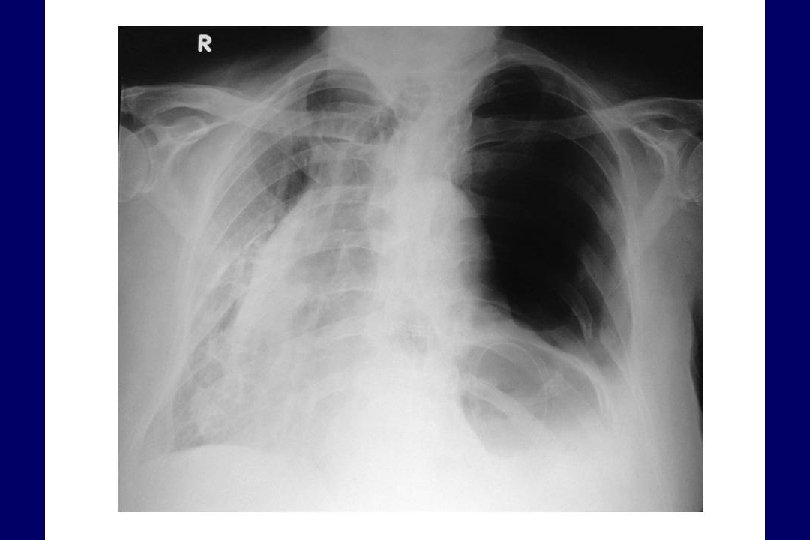

Tansiyon pnömotoraks • Aynı taraftaki akciğerin kollabe olması • Mediyasten ve trakeanın karşı tarafa itilmesi • Venöz dönüşün bozulması • Karşı akciğere bası 4 Akciğer veya göğüs duvarından tek yönlü valv şeklinde hava kaçağı 4 Tanısı kesinlikle klinik olarak konulur (radyolojik değil)

Tension Pneumothorax

Tansiyon pnömotoraks klinik tablo • • Respiratuvar distres Taşikardi Hipotansiyon Trakeal deviasyon Solunum seslerinin tek taraflı kaybı Boyun venlerinin distansiyonu Siyanoz (geç dönemde) Perküsyonla hiperrezonans* (kalp tamponadından ayırmada önemli)

Tansiyon pnömotoraks ayırıcı tanı kalp tamponadı

Tansiyon pnömotoraks tedavisi • Acil toraks dekompresyonu (geçici olarak midklavikular 2. interkostal aralığa iğne batırılarak uygulanan bu işlem olayı basit pnömotoraksa çevirir) • Toraks tüpü takılması (kesin tedavi, 5. interkostal aralıktan midaksiller hattın anterioruna takılır)